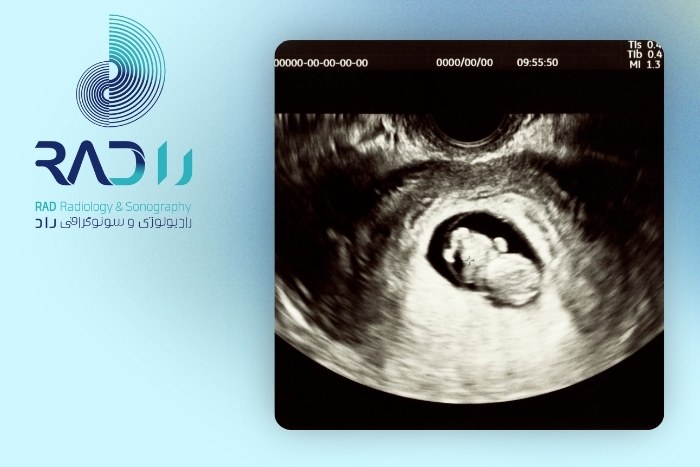

سونوگرافی اولیه (هفته ۶ تا ۸ بارداری)

تأیید وجود جنین داخل رحممشاهده ضربان قلب جنین

تشخیص چندقلویی (در صورت وجود بیش از یک جنین)

بررسی رحم، جفت اولیه و تخمدانها

معمولاً بهصورت واژینال انجام میشود تا تصویر واضحتری از جنین دیده شود.